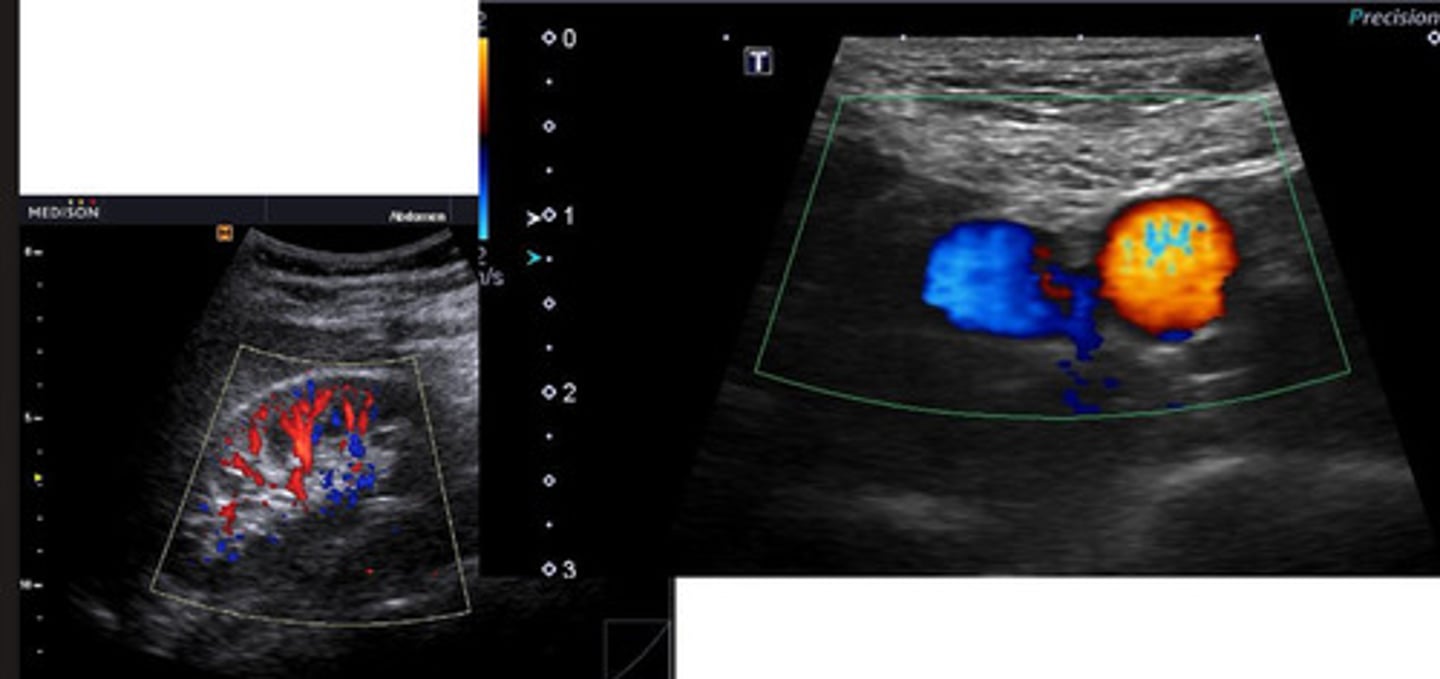

hilar

______ blood flow may be visualized with doppler (lymph nodes)

ID lymph node

medial iliac lns.

ID lymph node (hint: trifurcation near)

jejunal lns.

left- neoplasia

right- normal/reactive

which medial iliac ln. is neoplastic and which is normal/reactive?

lymphoma

which abnormality is this?